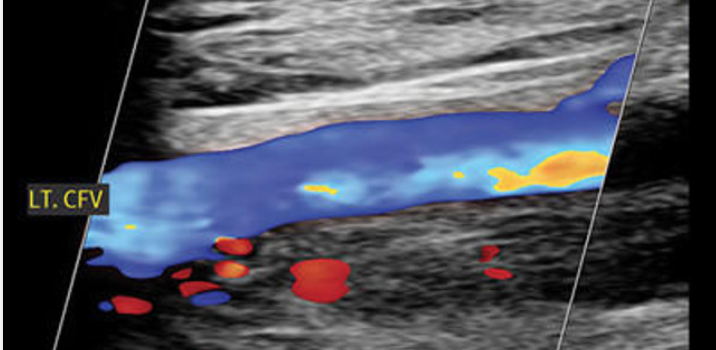

123sonography BachelorClass VASCULAR LOWER EXTREMITY Non-Invasive Vascular Ultrasound 01. MAYO CLINIC Cardiovascular Board Review for Initial Certification and Recertification, August 17-22, 2024 2023 MAYO Cardiovascular Online Board Review Mayo Clinic Cardiovascular Online Board Review 2022 Mayo Clinic Cardiovascular online Board